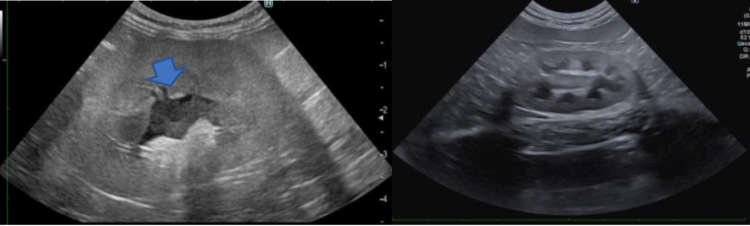

左:腫大し腎盂(青矢印、腎臓の中の尿が通る部分)が拡張した左腎、右:正常な腎臓